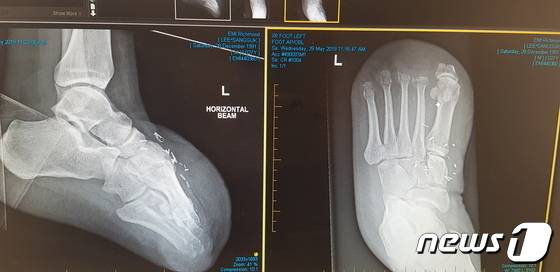

이씨가 탄 선박은 호주 멜버른항으로 이동·정박해 메인엔진 크로스헤드 베어링 결함 수리를 진행했다. 이 과정에서 2019년 3월12일 선박 내 체인블럭이 파손되면서 약 40m가량 공중으로 들어 올려져 있던 6톤 무게의 부품(크로스헤드 핀)이 이씨의 발등 위로 떨어져 발가락 10개가 모두 절단됐다. 취업한 지 26일 만이다.

사고 직후 이씨는 발가락을 접합할 수 있는 골든타임을 놓친 채 호주 병원으로 이송, 현재까지 홀로 현지에서 재활치료를 받고 있다.